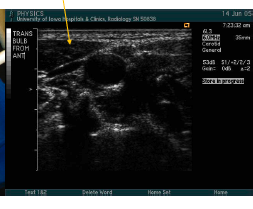

what are teh arrows pointing to here? what image is being taken?

trans CCA mid